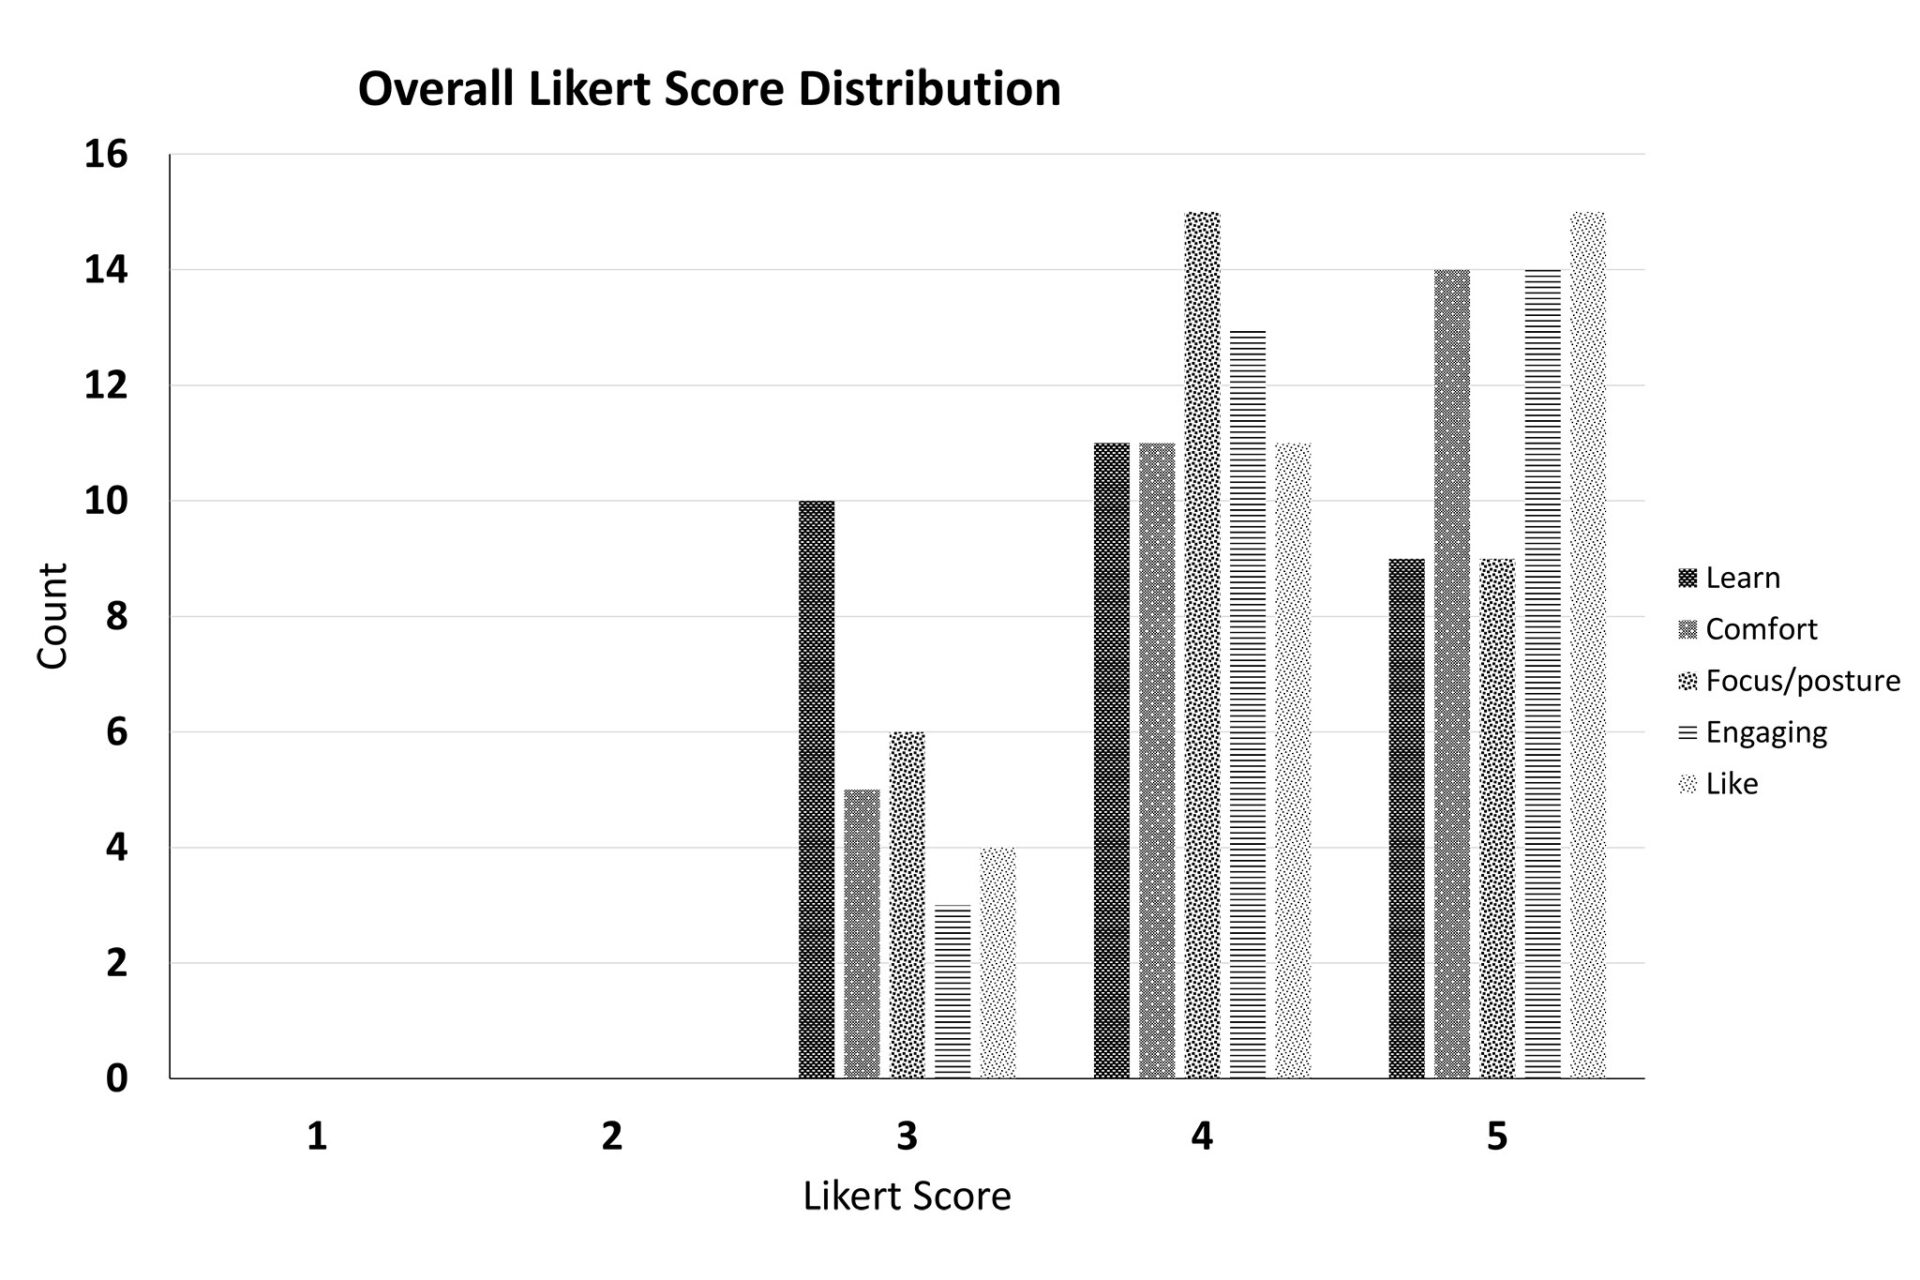

Virtual Reality Perimeters A More Comfortable, Engaging and User-Friendly Alternative

Assesses patient experience across comfort, focus, and engagement to identify how VR-based perimetry can improve accessibility and satisfaction in clinical care. (NANOS 2024)

Virtual Reality Perimeters A More Comfortable, Engaging and User-Friendly Alternative

Assesses patient experience across comfort, focus, and engagement to identify how VR-based perimetry can improve accessibility and satisfaction in clinical care. (NANOS 2024)